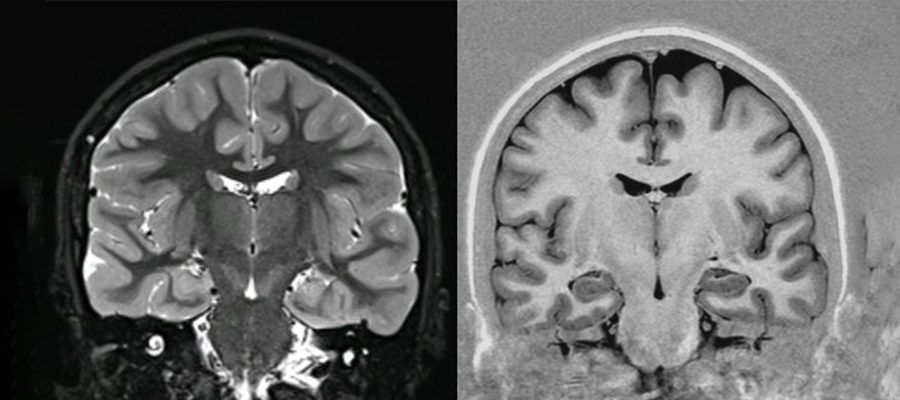

Açık EMAR Görüntü Kalitesi Yeterli mi?

Güncel teknolojiyle üretilmiş açık EMAR cihazları;

Beyin

Omurga

Eklem

Ortopedik incelemeler

gibi birçok alanda tanısal açıdan yeterli kalite sunar. Doktorunuzun yönlendirmesiyle hangi EMAR türünün uygun olduğu netleşir.